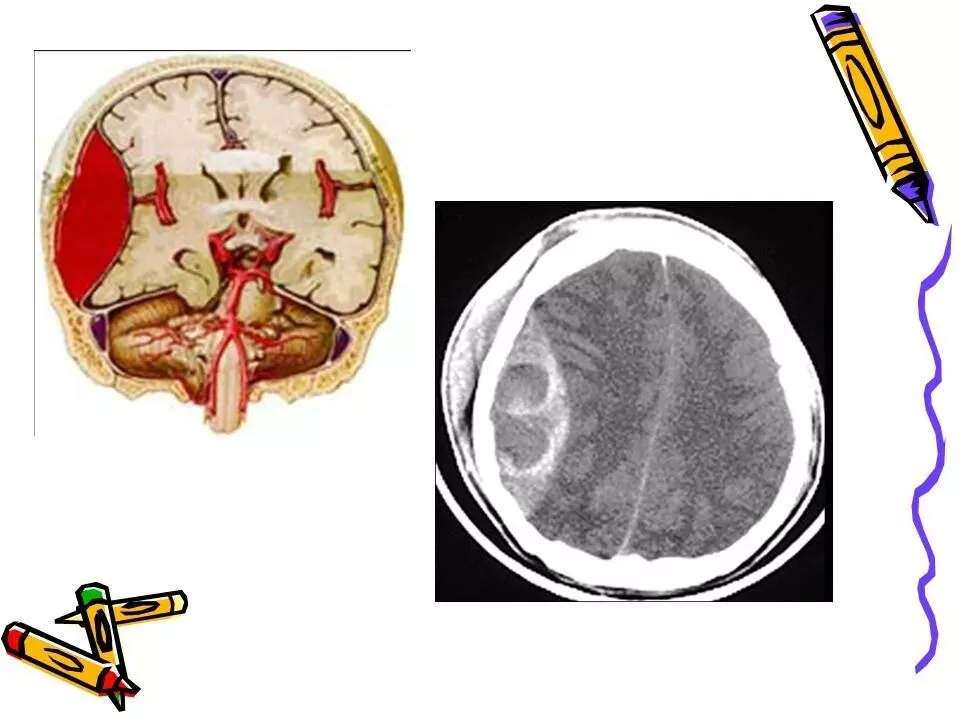

>常见颅脑外伤CT诊断(PPT)

常见颅脑外伤CT诊断(PPT)